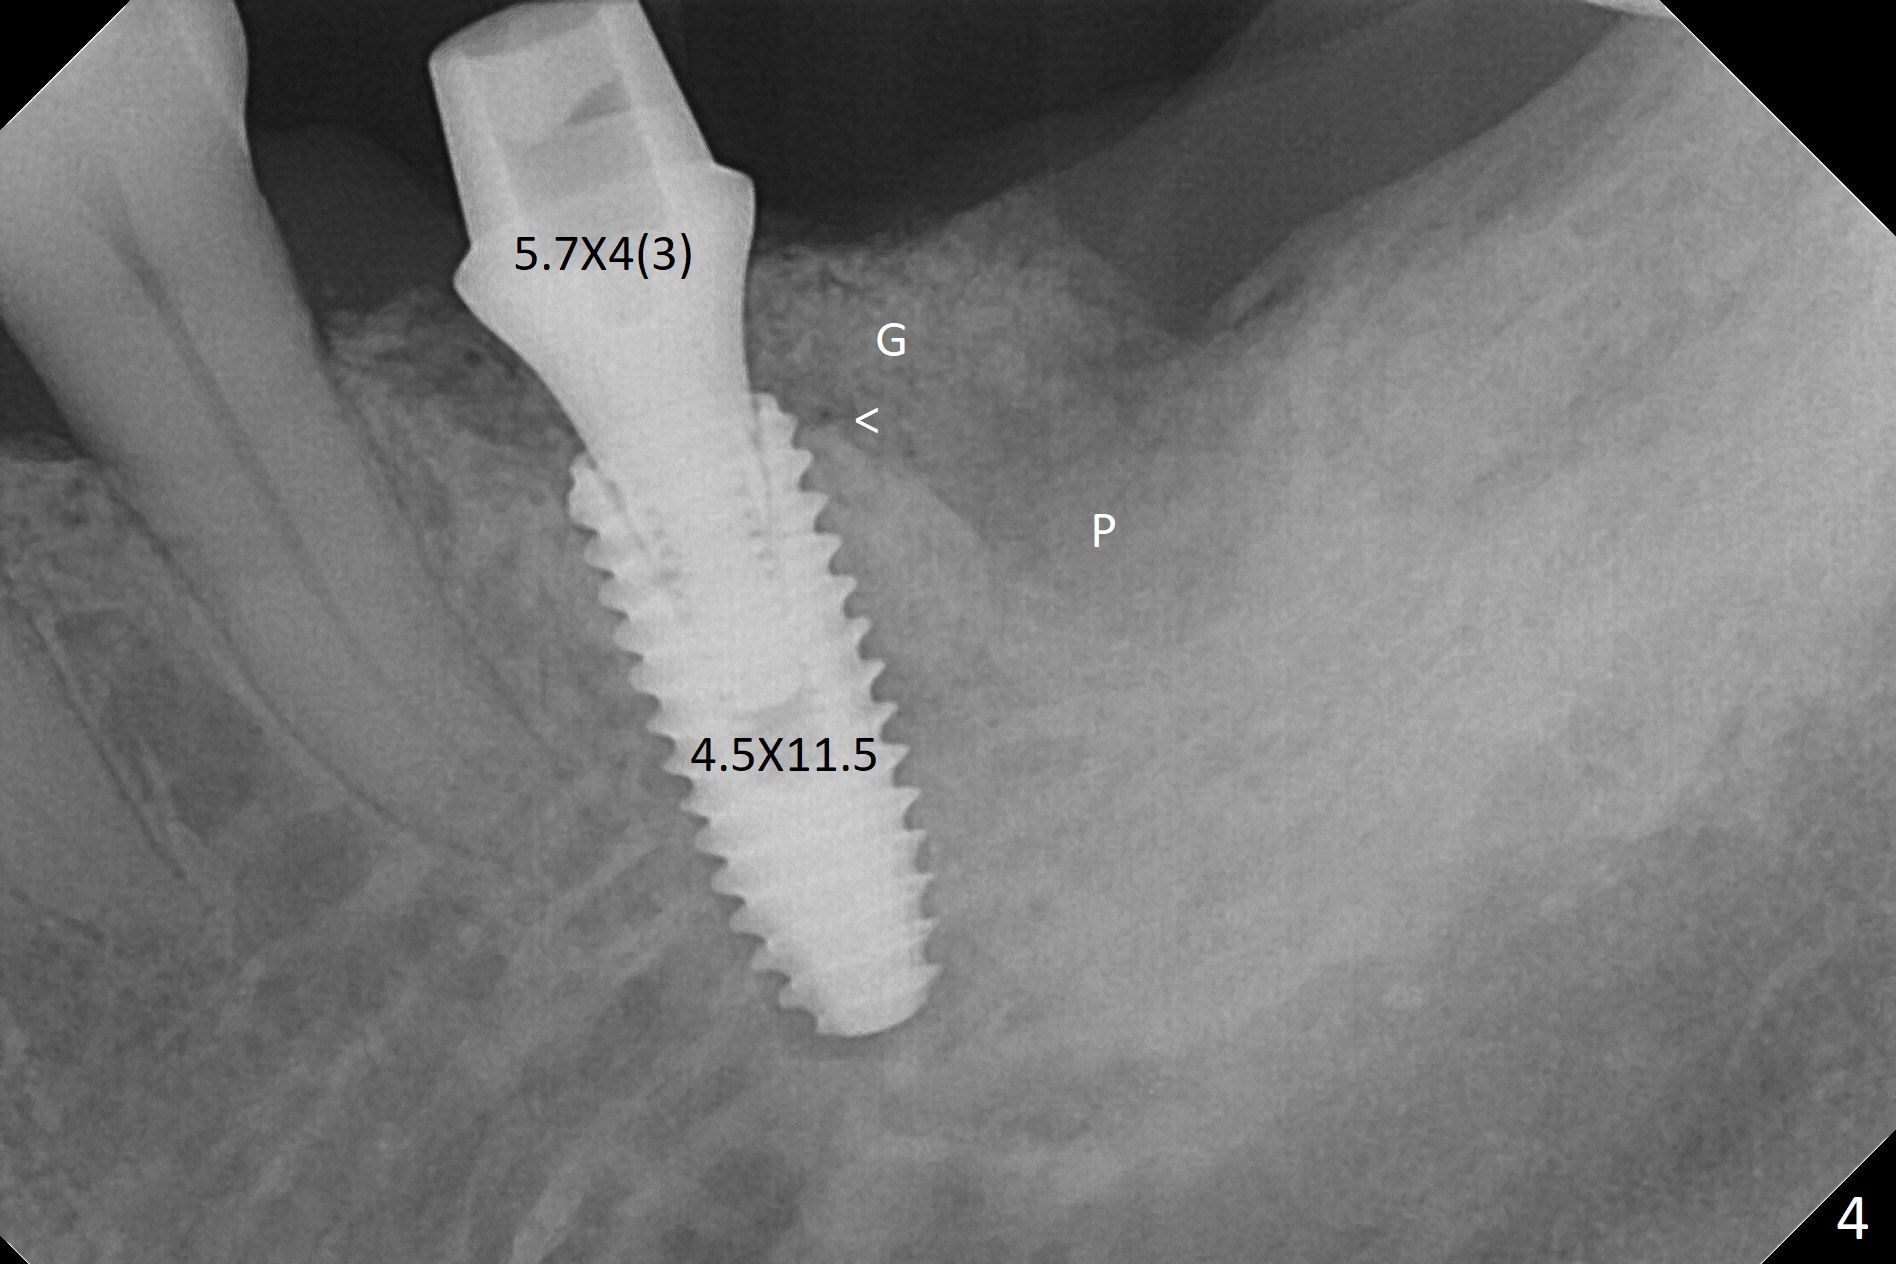

A 68-year-old man returns for extraction of the tooth #19 with distal root periodontal-endodontic lesion (Fig.1 *). After discussion, he agrees immediate implant. A 4.5x11.5 mm implant will be placed in the mesial socket (Fig.2 (red line: superior border of Inferior Alveolar Canal)); the plateau level with the septal crest (<). Osteotomy is initiated in the lingual slope of the mesial socket; the depth is controlled with stopper (Fig.3 S). The implant is placed at the level as expected (Fig.4 <) with insertion torque ~30 Ncm; after placement of 5.7x4(3) mm abutment and Osteogen plug (P) in the apical half of the distal socket, bone graft (G) is placed in the remaining socket gaps, mainly distal and buccal. An immediate provisional is fabricated to keep the graft in place (Fig.5 T). The graft may be lost if the gingival margin recedes in healing. Periodontal dressing is applied for additional security (Fig.6). There is no postop paresthesia. The upper border of the Inferior Alveolar Canal in Fig.3,4 seems to be high. In fact it may be a branch of the Inferior Alveolar Canal (Fig.7 yellow line, as compared to Fig.4). With all of measures taken (including periodontal dressing), the distal bone graft (Fig.8 *) is ~ 2 mm coronal to the crestal bone (red line) 6 months postop. The temporary crown is perforated. The gingival cuff is erythematous. A 6.8x5 mm healing abutment is installed. When the patient returns for impression, a 4.5x5.5(3) mm abutment is fully seated (Fig.9 <). The distal height increases by 4 mm because of immediate implant (support). The mesial papilla remains normal in height and shape immediate post cementation (Fig.10), as related to the mesial socket implant placement without mesial crestal bone loss. The mesial and distal crestal height is maintained 13 months post cementation (Fig.11, weight lifter).